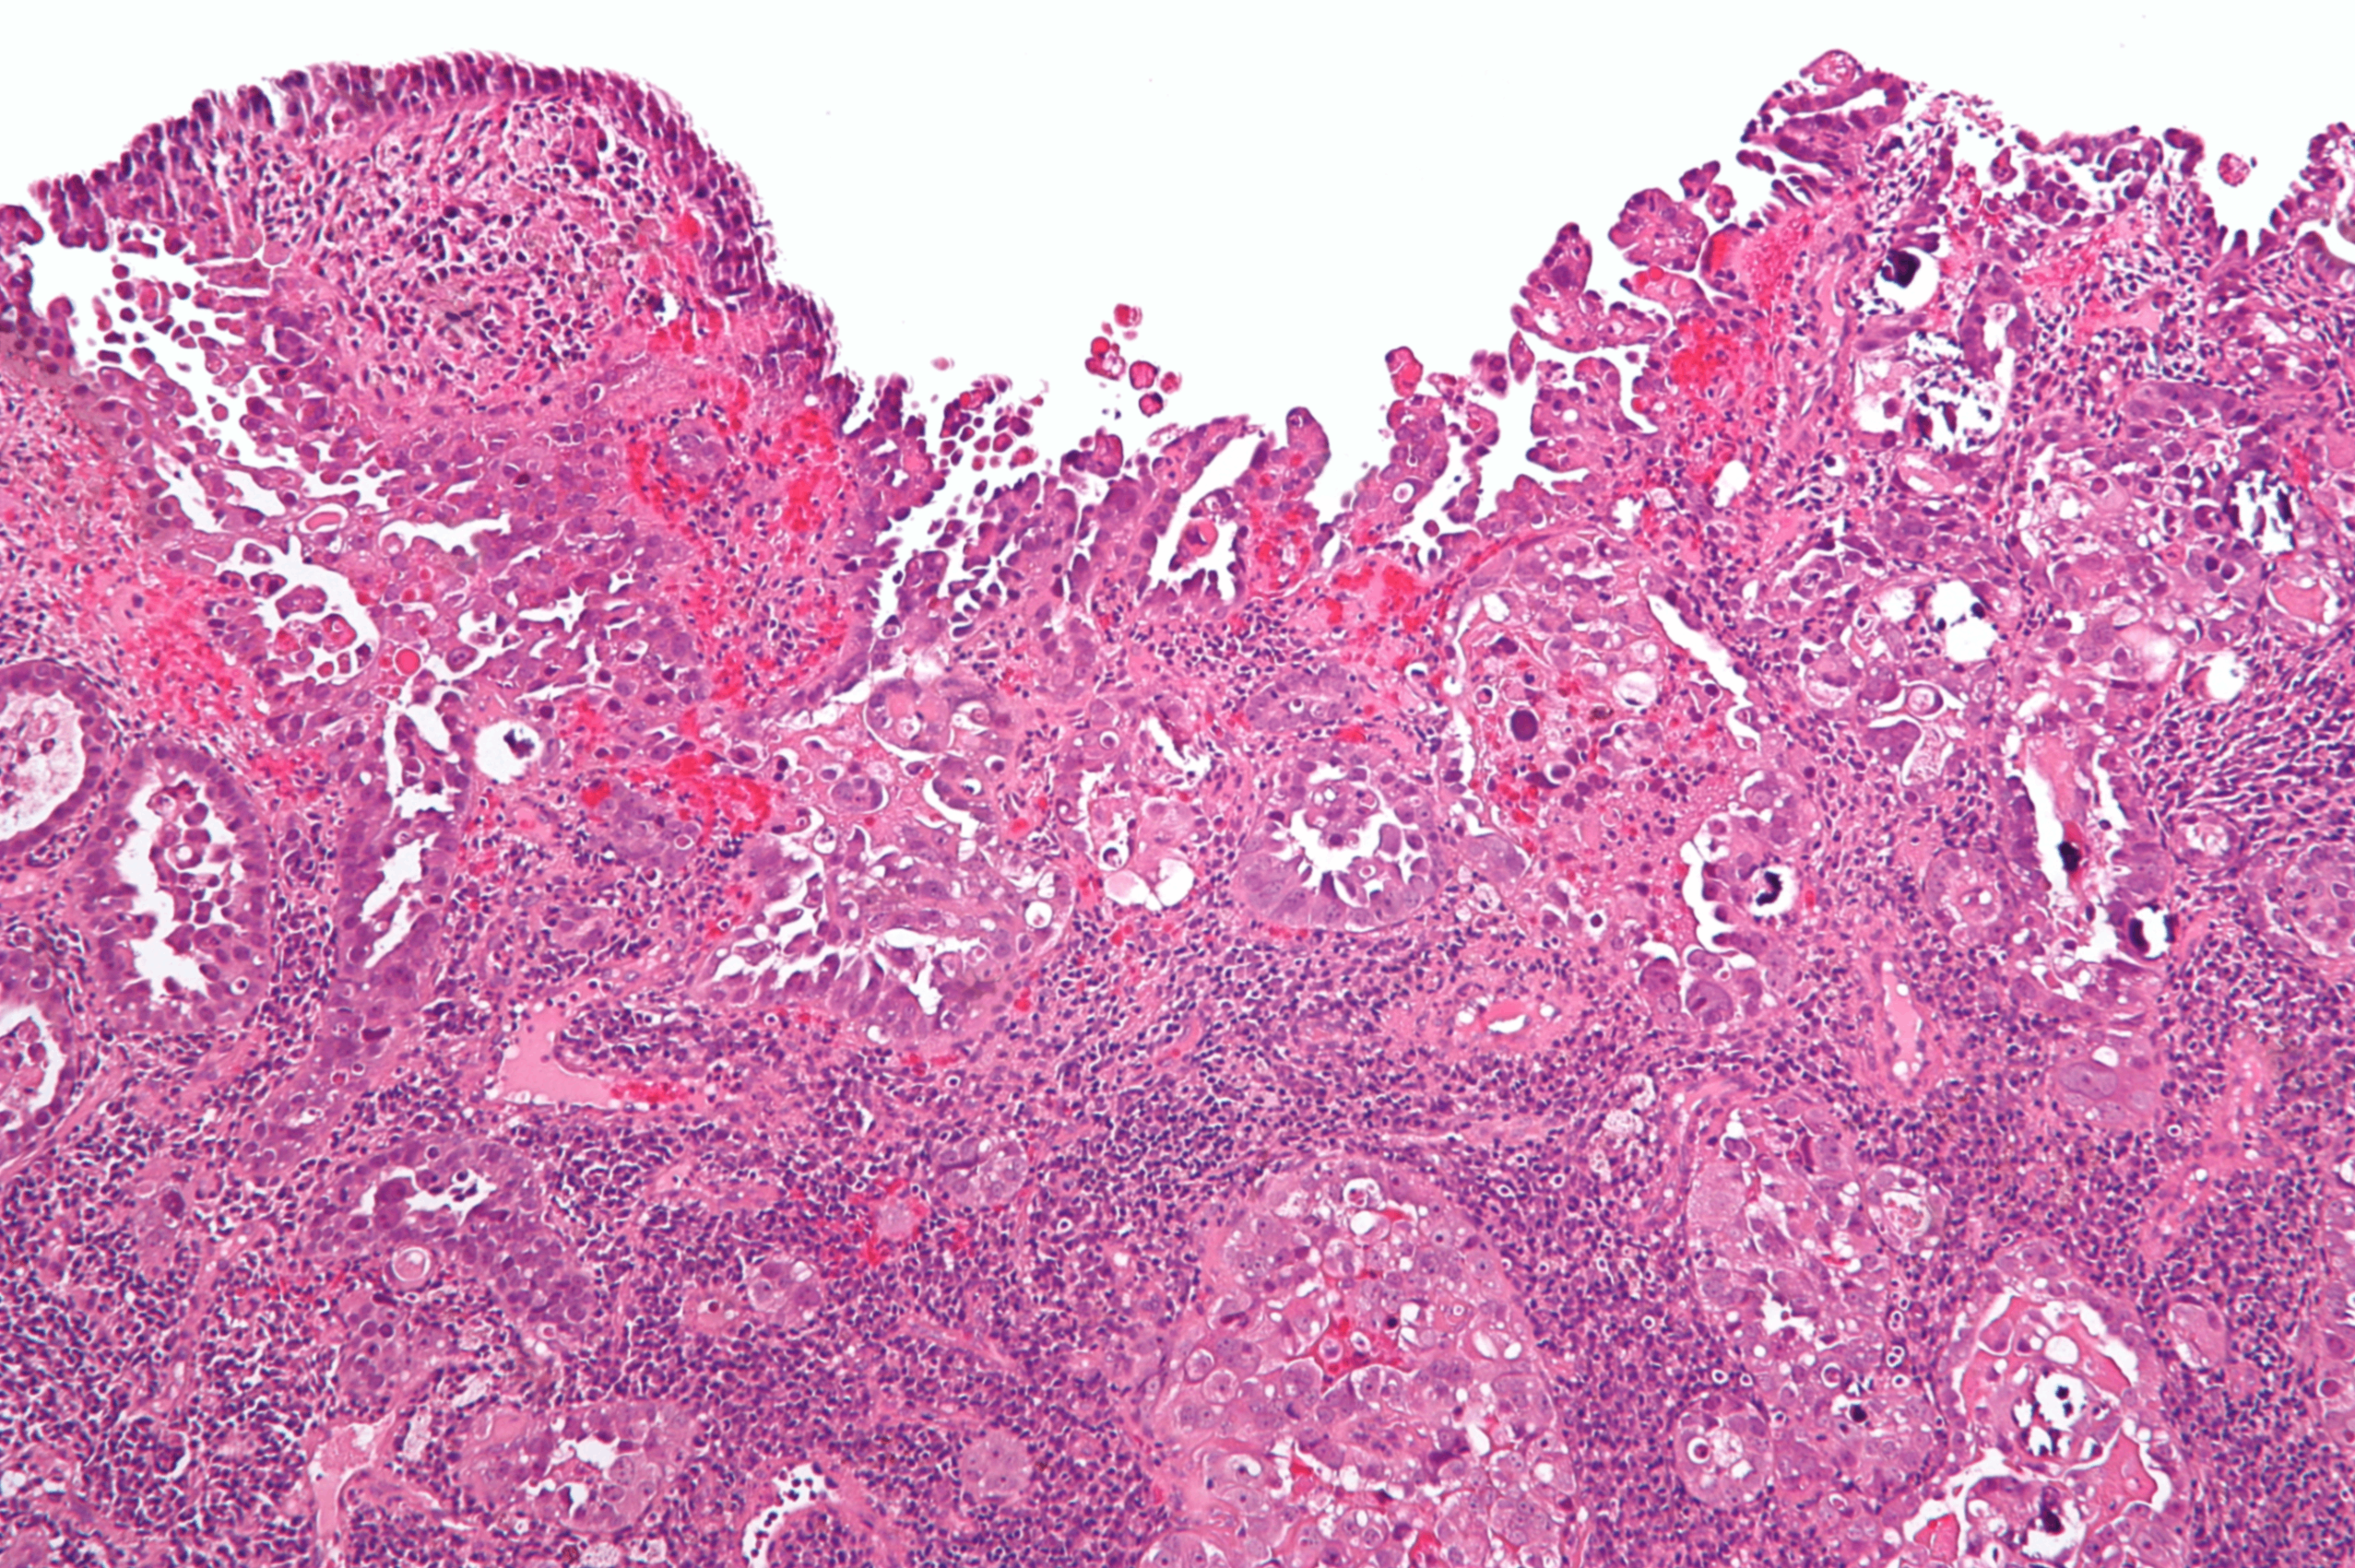

② 자궁내막선암

• 자궁에 발생하는 암 중 가장 흔한 유형 (80-85%)

• 자궁내막증식에서 진행됨

• 다름 암들과 마찬가지로, 자궁내막선암의 발병은 단계적인 유전자 변이 축적에 기인함. 특히 PI3K/AKT 경로의 유전자 변이들이 중요한 역할을 수행

Robbins and Cotran Pathologic Basis of Disease, 10e, pg 1009

• 등급이 높아질수록 선조직의 형태가 없어지고 solid growth pattern과 squamous differentiation을 보임

Endometrioid endometrial carcinoma, Wikipedia Commons